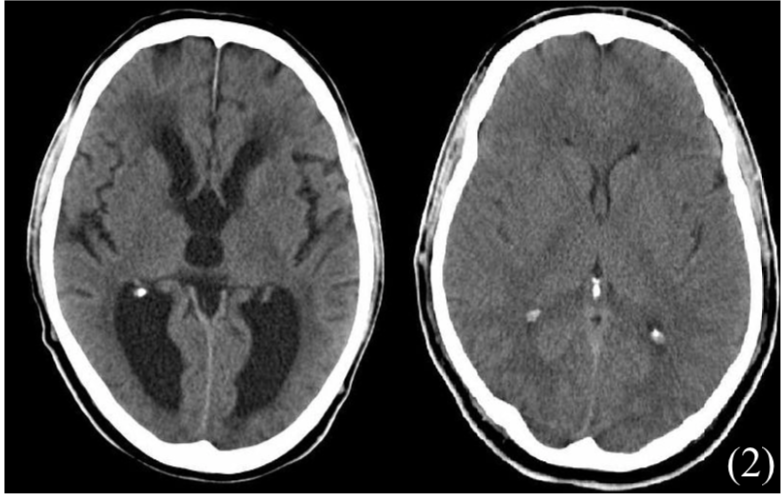

– Imaging – CT head (structural causes) and MRI (vasculature changes)

CT/MRI scan

c) Normal Pressure Hydrocephalus:

A special type which gives large ventricle but normal ICP

– Triad of urinary incontinence, gait instability + dementia

1st CT head